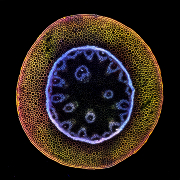

Motýl |  Znx(PO4)y-albumin r�... |  Neurální rozety |  The Experimentalist |